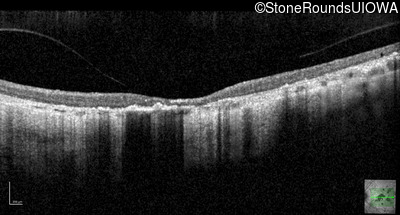

Optical Coherence Tomography - Right - 20/200 sc

Exemplar / OCT Stack

OCT Stack

Optical Coherence Tomography - Left - 20/250 sc